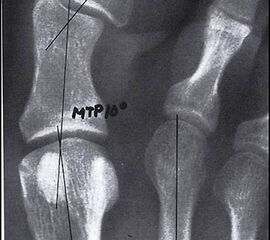

Wenn durch das Anspannen der Muskulatur der 1. Strahl zu einem starren Hebel wird und aussteift, empfehlen wir auf die Durchführung einer TMT-I-Arthrodese zu verzichten und z.B. eine proximale Korrekturosteotomie durchzuführen. So ist nach unserer Auffassung bei jeglicher Dorsalbewegung des 1. Strahles (Instabilität) trotz Anspannung der Peronealmuskulatur (wie beschrieben) die Indikation zur Lapidusarthrodese unabhängig vom Intermetatarsalwinkel gegeben. Bei der Beurteilung des a.p.-Röntgenbildes unter Belastungsbedingungen dient die Bestimmung des Hallux valgus interphalangeus-Winkes und des distalen Artikulationswinkels ggf. zur Indizierung einer additiven Akin-Osteotomie (Abb. 4). Die Stellung des proximalen Artikulationswinkels legt im Falle einer bereits praeoperativ bestehenden Vergrößerung nach Korrektur des Intermetatarsalwinkels eine Korrektur durch eine Reverdin-Green-Laird-Osteotomie nahe (Abb. 5). Die Größe des Intermetatarsalwinkels I/II beeinflusst je nach Größe bei stabilem 1. Strahl die Wahl des jeweiligen Operationsverfahrens.

Im Falle einer Insuffizienz des 1. Strahles wird in jedem Falle eine TMT-I-Arthrodese indiziert sein, hier dient der Intermetatarsalwinkel planerischen Aspekten im Sinne des Ausmaßes der Korrektur am Os cuneiforme I. Die Bestimmung des Metatarsus adductus-Winkels dient der Detektion eines Pes adductus. Im Falle des Vorliegens einer solchen Deformität sind ggf. auch Korrekturosteotomien an den kleineren Metatarsalia zu erwägen, um ausreichend Platz für die Einstellung des Metatarsale I in die Rectusposition zu erhalten. Ein weiteres wichtiges Kriterium in der a.p.-Projektion stellt das Längenverhältnis von Metatarsale I zu Metatarsale II dar, da bei der Durchführung der TMT-I-Arthrodese das Vorliegen einer Minusvariante häufiger die Gefahr einer postoperativen Transfermetatarsalgie birgt und hier unter Umständen über Modifikationen des operativen Vorgehens nachgedacht werden sollte. Hier besteht die Möglichkeit von alternativen Präparationsverfahren im TMT I oder aber der Durchführung einer Interpositionsarthrodese des TMT I zur Verlängerung des 1. Strahles. Alternativ können auch Verkürzungsosteotomien des 2. und 3. Strahles erwogen werden. Als indirekte radiologische Zeichen einer Insuffizienz des 1. Strahles kann ein Klaffen des Spaltes zwischen dem Os cuneiforme mediale und dem Os cuneiforme intermedium sowie eine Hypertrophie der Corticalaes des Metatarsale II gedeutet werden (Abb. 6).